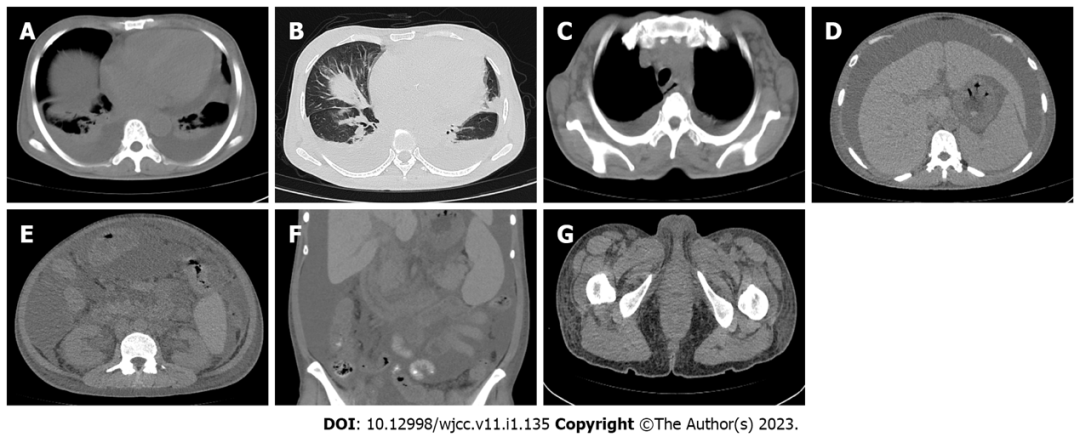

影像学检查:2021-11-12复查胸腹部CT示(图3):1)双侧胸膜增厚,双侧胸腔少-中量积液,双肺多发散在炎性改变,明显多于2021-03-16所见;2)心脏较早期图像增大,心包中度积液较早期图像明显;3)纵隔、双侧腋窝及腹股沟、腹膜后多发淋巴结显示,部分肿大;4)肝脏饱满,肝脏左右叶比例失调;脾大,腹盆腔积液,较前积液增多,胃肠道壁增厚,腹盆腔内脂肪间隙模糊,双肾周筋膜增厚、紊乱,腰腹部及臀部软组织水肿。

图3. 2021年11月12日胸部和腹部CT

A:双侧胸腔积液,双肺下叶肺不张,心脏增大心包积液;B:双肺多发炎性病变,双侧胸膜稍增厚,左叶裂少量积液;C:双侧腋窝淋巴结增大;D:肝大、腹水、脾大和肝囊肿;E:腹膜后淋巴结肿大和肾周膜筋膜增厚;F:腹盆腔积液、胃肠壁增厚,腹腔及盆腔脂肪间隙模糊;G:双侧腹股沟淋巴肿大,腰部、腹部和臀部软组织水肿